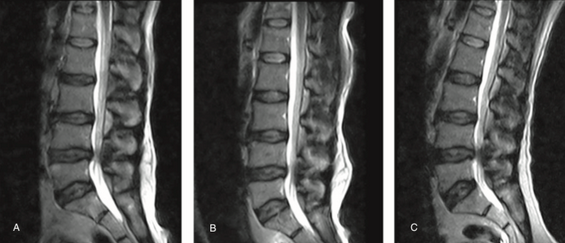

腰椎滑脱该怎么诊治?看这篇就够了!

腰椎滑脱是一种比较常见的疾病,是指其中一节段椎体与下方椎体向前滑动或脱离。